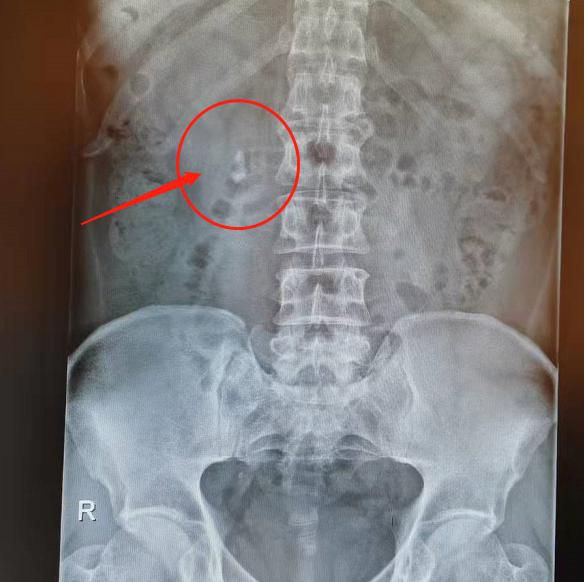

△體外碎石前。

△體外碎石後。